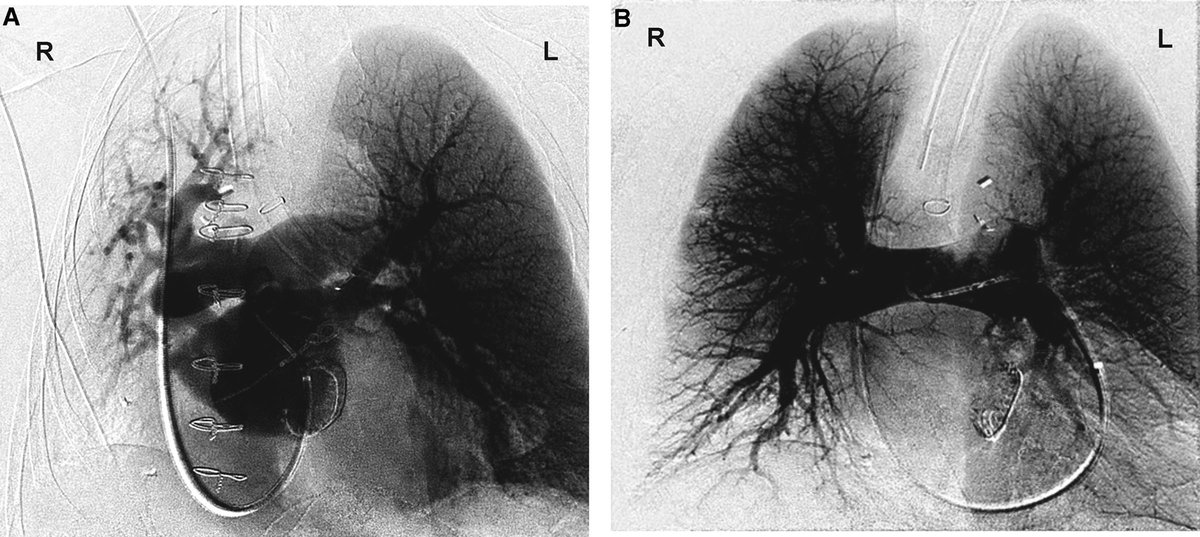

Figure 2 from Management of pulmonary aspiration due to undiagnosed Pulmonary Aspiration Anesthesia The inhalation of oropharyngeal or gastric contents into the larynx and the respiratory tract. perioperative pulmonary aspiration is defined as aspiration of gastric contents occurring after induction of anesthesia, during a procedure, or in. The materials that can be. although pulmonary aspiration complicating operative general anaesthesia has been extensively studied, little is known regarding. pulmonary aspiration was. Pulmonary Aspiration Anesthesia.